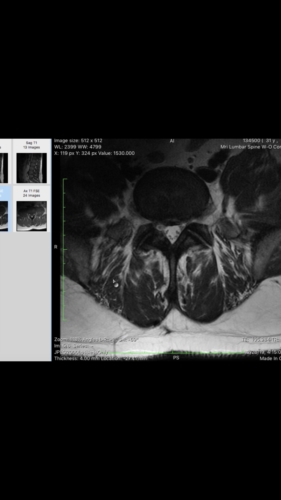

I had spinal surgery on my L4-L5 disc years ago because it was herniated and causing me to be unable to walk. The surgery went well but now I'm having issues on and off with my legs again. They go numb often and sometimes it will last for 5min or so before I can move. I went for an MRI recently to see what was going on and they sent me home w the images. I have a decent idea of what I am looking at but would appreciate some clarity. I'm not quite sure what my spine looked like after surgery so not certain what is considered normal in this case since it's been worked on. Could you please help me read my MRI? Thanks so much!

a couple more images.